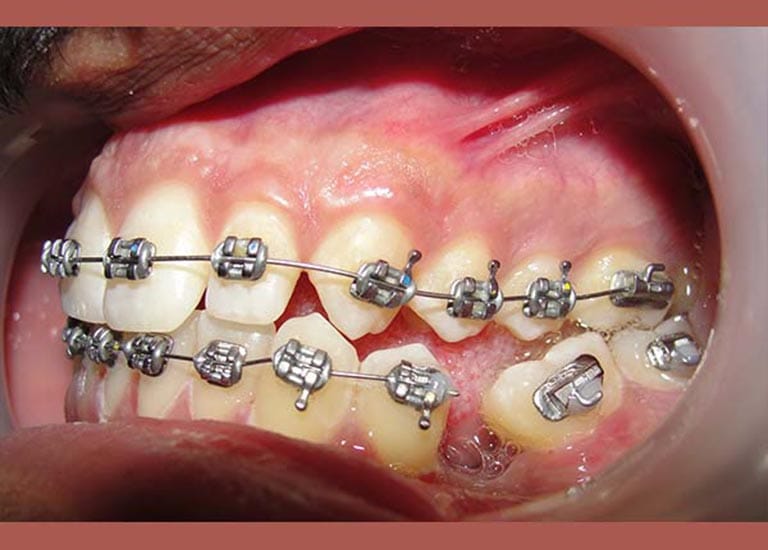

حالة رحى سفلية منطمرة و مائلة في الطرف الأيمن تم تعديلها تقويمياً و رحى سفلية مائلة في الطرف الأيسر أيضاً تم تعديلها تقويمياً